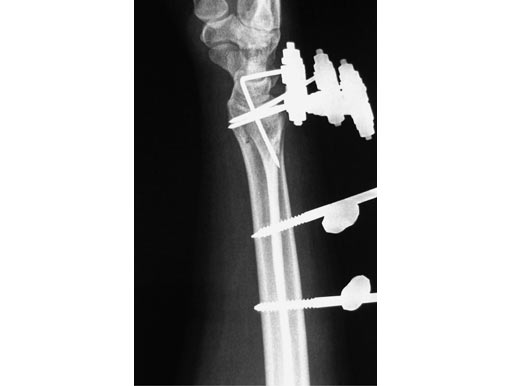

Nonspanning Distal Radius Fixator

Treatment of fractures of the distal radius has been proven to be advantageous if spanning of the wrist joint is avoided. This allows for greater motion throughout the treatment resulting in improved range of motion, grip strength, and dexterity. The nonspanning Distal Radius Fixator provides such a nonbridging external fixator, creating a low-profile frame for increased patient comfort and the ability to perform daily activities.

The nonspanning Distal Radius Fixator consists of a small adjustable clamp, nonspanning, MR safe. It locks on to two 4.0 mm Schanz Screws spaced 20 mm apart. The 4.0 mm carbon fiber rod slides into a through hole in the clamp with a set screw tightening point to established the desired length. A ball joint in the clamp then provides for ulnar/radial as well as volar/dorsal deviation of the rod. To create lower profile frames, the nonspanning Distal Radius Fixator includes three shorter length Schanz screws65 mm lengths in both 4.0/2.5 mm size (with a trocar tip) and the 4.0/3.0 mm size (with a self-drilling tip), and an 80 mm length in the 4.0/2.5 mm size (with a trocar tip).

The 4.0 mm curved carbon fiber rods match the axial curvature of the wrist. They are available in 60, 90, 120, or 180 arcs to be used for fixation of the distal fragment.

The 4.0 mm angled T-bar carbon fiber rods create the same angle as the curved rods, with the addition of a rod extending perpendicularly. The material allows a frame to be constructed with a rod centred on the dorsal aspect of the wrist without sacrificing the C-arm image in the dorsal/palmar view. The angled T-bar fiber rods will be available in 80 mm (length) 50 mm (width), 80 120 mm, 110 50 mm, and 110 120 mm. Both the curved and angled T-bar fiber rods can be used as part of a delta frame construct.

56-year-old female, accident at home